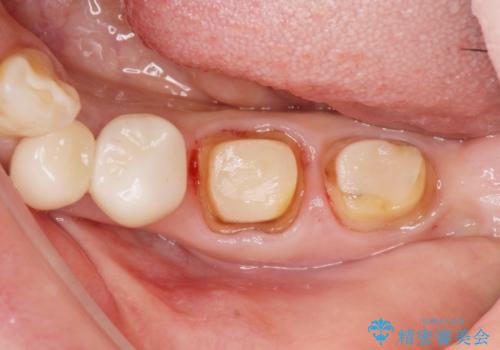

銀歯を除去したのち、虫歯を丁寧に除去し、歯を残せるのかどうかをしっかりと評価し、長期的な予後を見据えた虫歯治療を行っていきます。

銀歯の下で虫歯が再発していた歯は、無理に残しても割れてしまう可能性が非常に高いと考えたため、相談の上抜去を行いインプラント治療を行っていくこととしました。